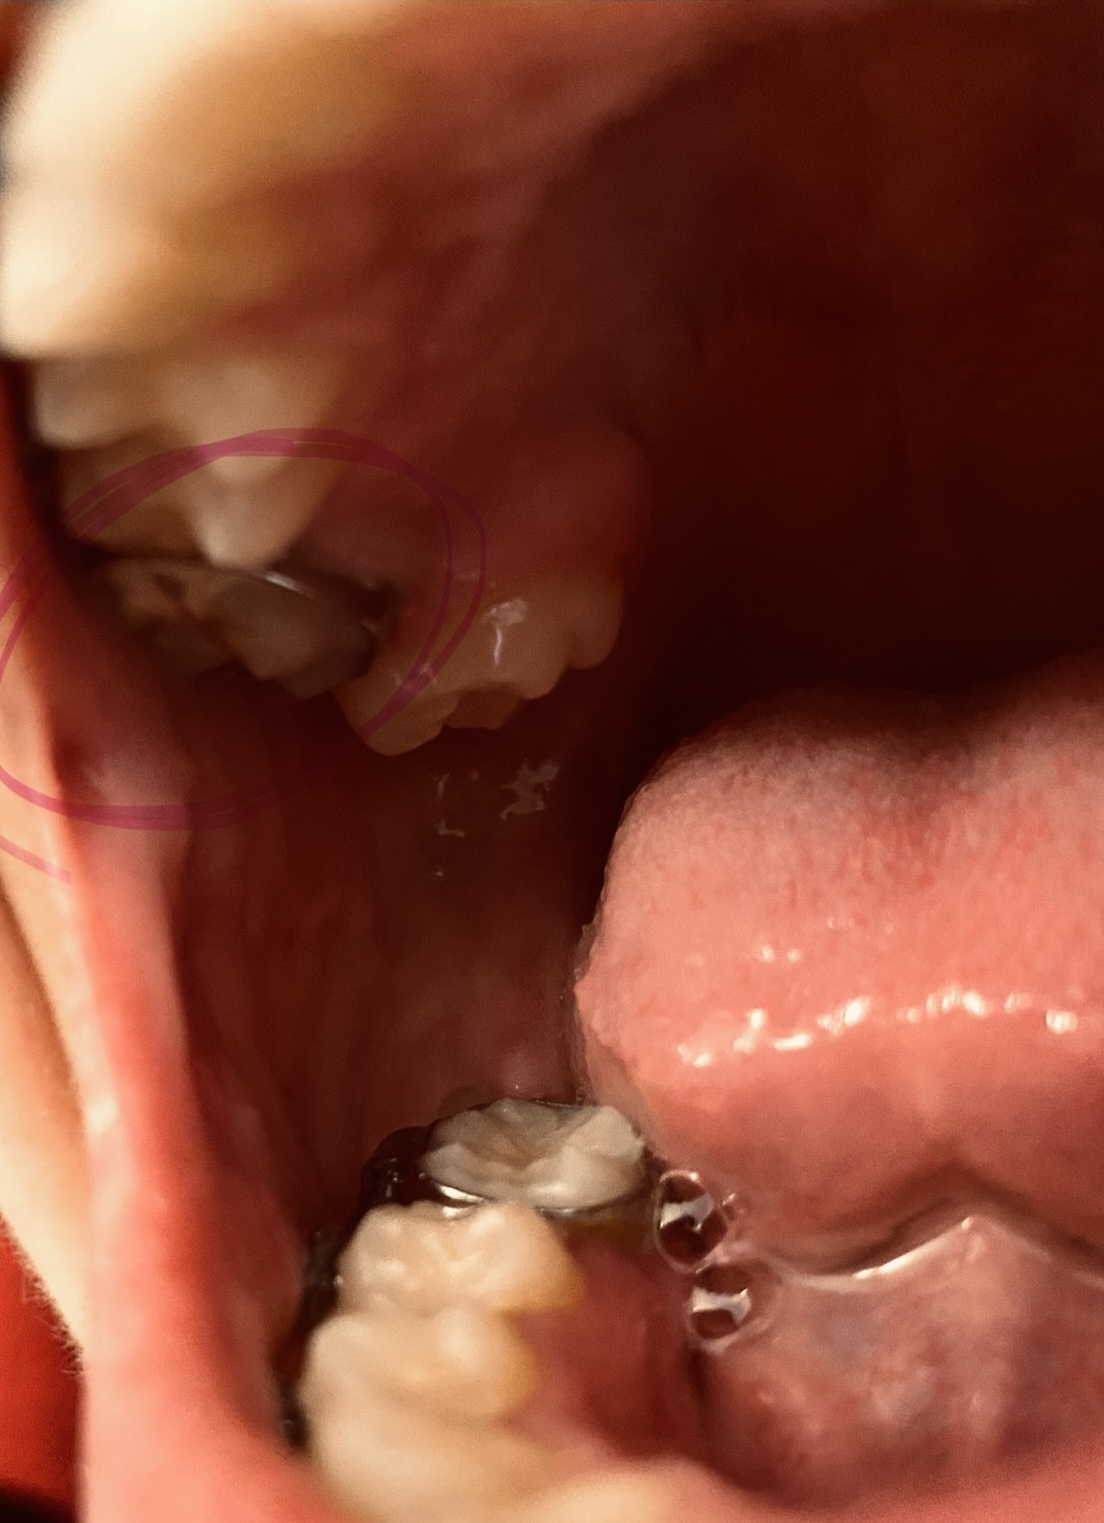

Extraction During Braces for Scissor Bite Molar

Hello, i have a simple question regarding braces, over crowding etc. im a 15 year old girl with braces that have been on for 2 years, i have a scissor bite due to a severe crowding case and i have big teeth, i also have an overbite but its not too...